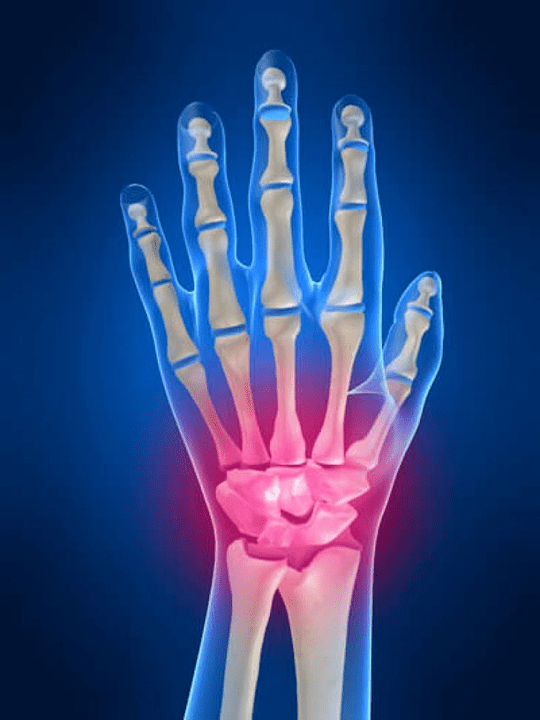

Joint painFingers are an indispensable sign of any joint pathology in which the structural components of these joints are damaged.First, pain in these joints may be associated with various autoimmune diseases (Systemic red gloss, rheumatoid arthritis, psoriatic arthritis and more.) in which the immune factors cause damage to their own joint tissues.

The next main reason that can startpainThere may be injuries in the joints of the fingers (bruises, dislocations, bone fractures, ties).The soreness in these joints can also be provoked by degenerative changes occurring in their joint tissues.This can often be observed in osteoarthritis.

Wrist

The junction is formed by the bones of the proximal bones (upper) A number of wrists (Triadic, semi -moons, scaphoid bones) and distal areas of radiation and elbow bones.The bone of the elbow is not directly related to the bones of the wrist, but with the help of distal (Less) The article disc.This structure separates the wrist cavity of the joint from the distal cavity (Less) Your own joint.

What structures can be inflamed in the joints of the hands?

Inflammation is a typical pathological process characteristic of these tissues and organs that have been damaged for some reason.It is worth remembering that in most cases any disease (For example gout, rheumatoid arthritis, etc.) or trauma that damages the joints of the hands to one degree or another affect not only the staccular but also the peroster (nerves, muscles, tendons, subcutaneous fat, skin) structures.

The following joint structures can be inflamed in the joints of the hands:

- joint cartilage;

- Squeezing bone tissue;

- joint capsule;

- Joint links.

The causes of pain in the joints of the arm and fingers

The main share of the causes causing pain in the joints of the arm and fingers is occupied by mechanical injuries (Fractures, dislocations, bruises and more.) and systemic autoimmune diseases (Rheumatoid arthritis, systemic lupus erythematosus, psoriasis and more.).In addition to these causes, soreness in the joints of the hands can cause diseases associated with metabolic disorders (For example, gout, osteoarthrosis).